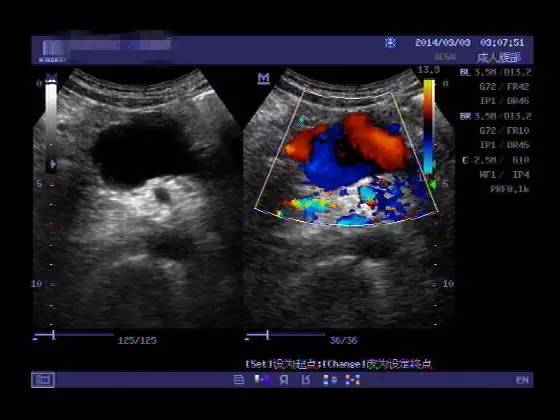

多普勒超声

无创、易行的检查,可明确有无腹主动脉瘤,以及瘤体的部位和大小。所以彩超对筛查、定期观察、术后的病人的随访非常有价值。医博士建议65岁以上老人可通过超声进行腹主动脉瘤筛查,而家族中有腹主动脉瘤史的亲属则宜50岁开始进行筛查。